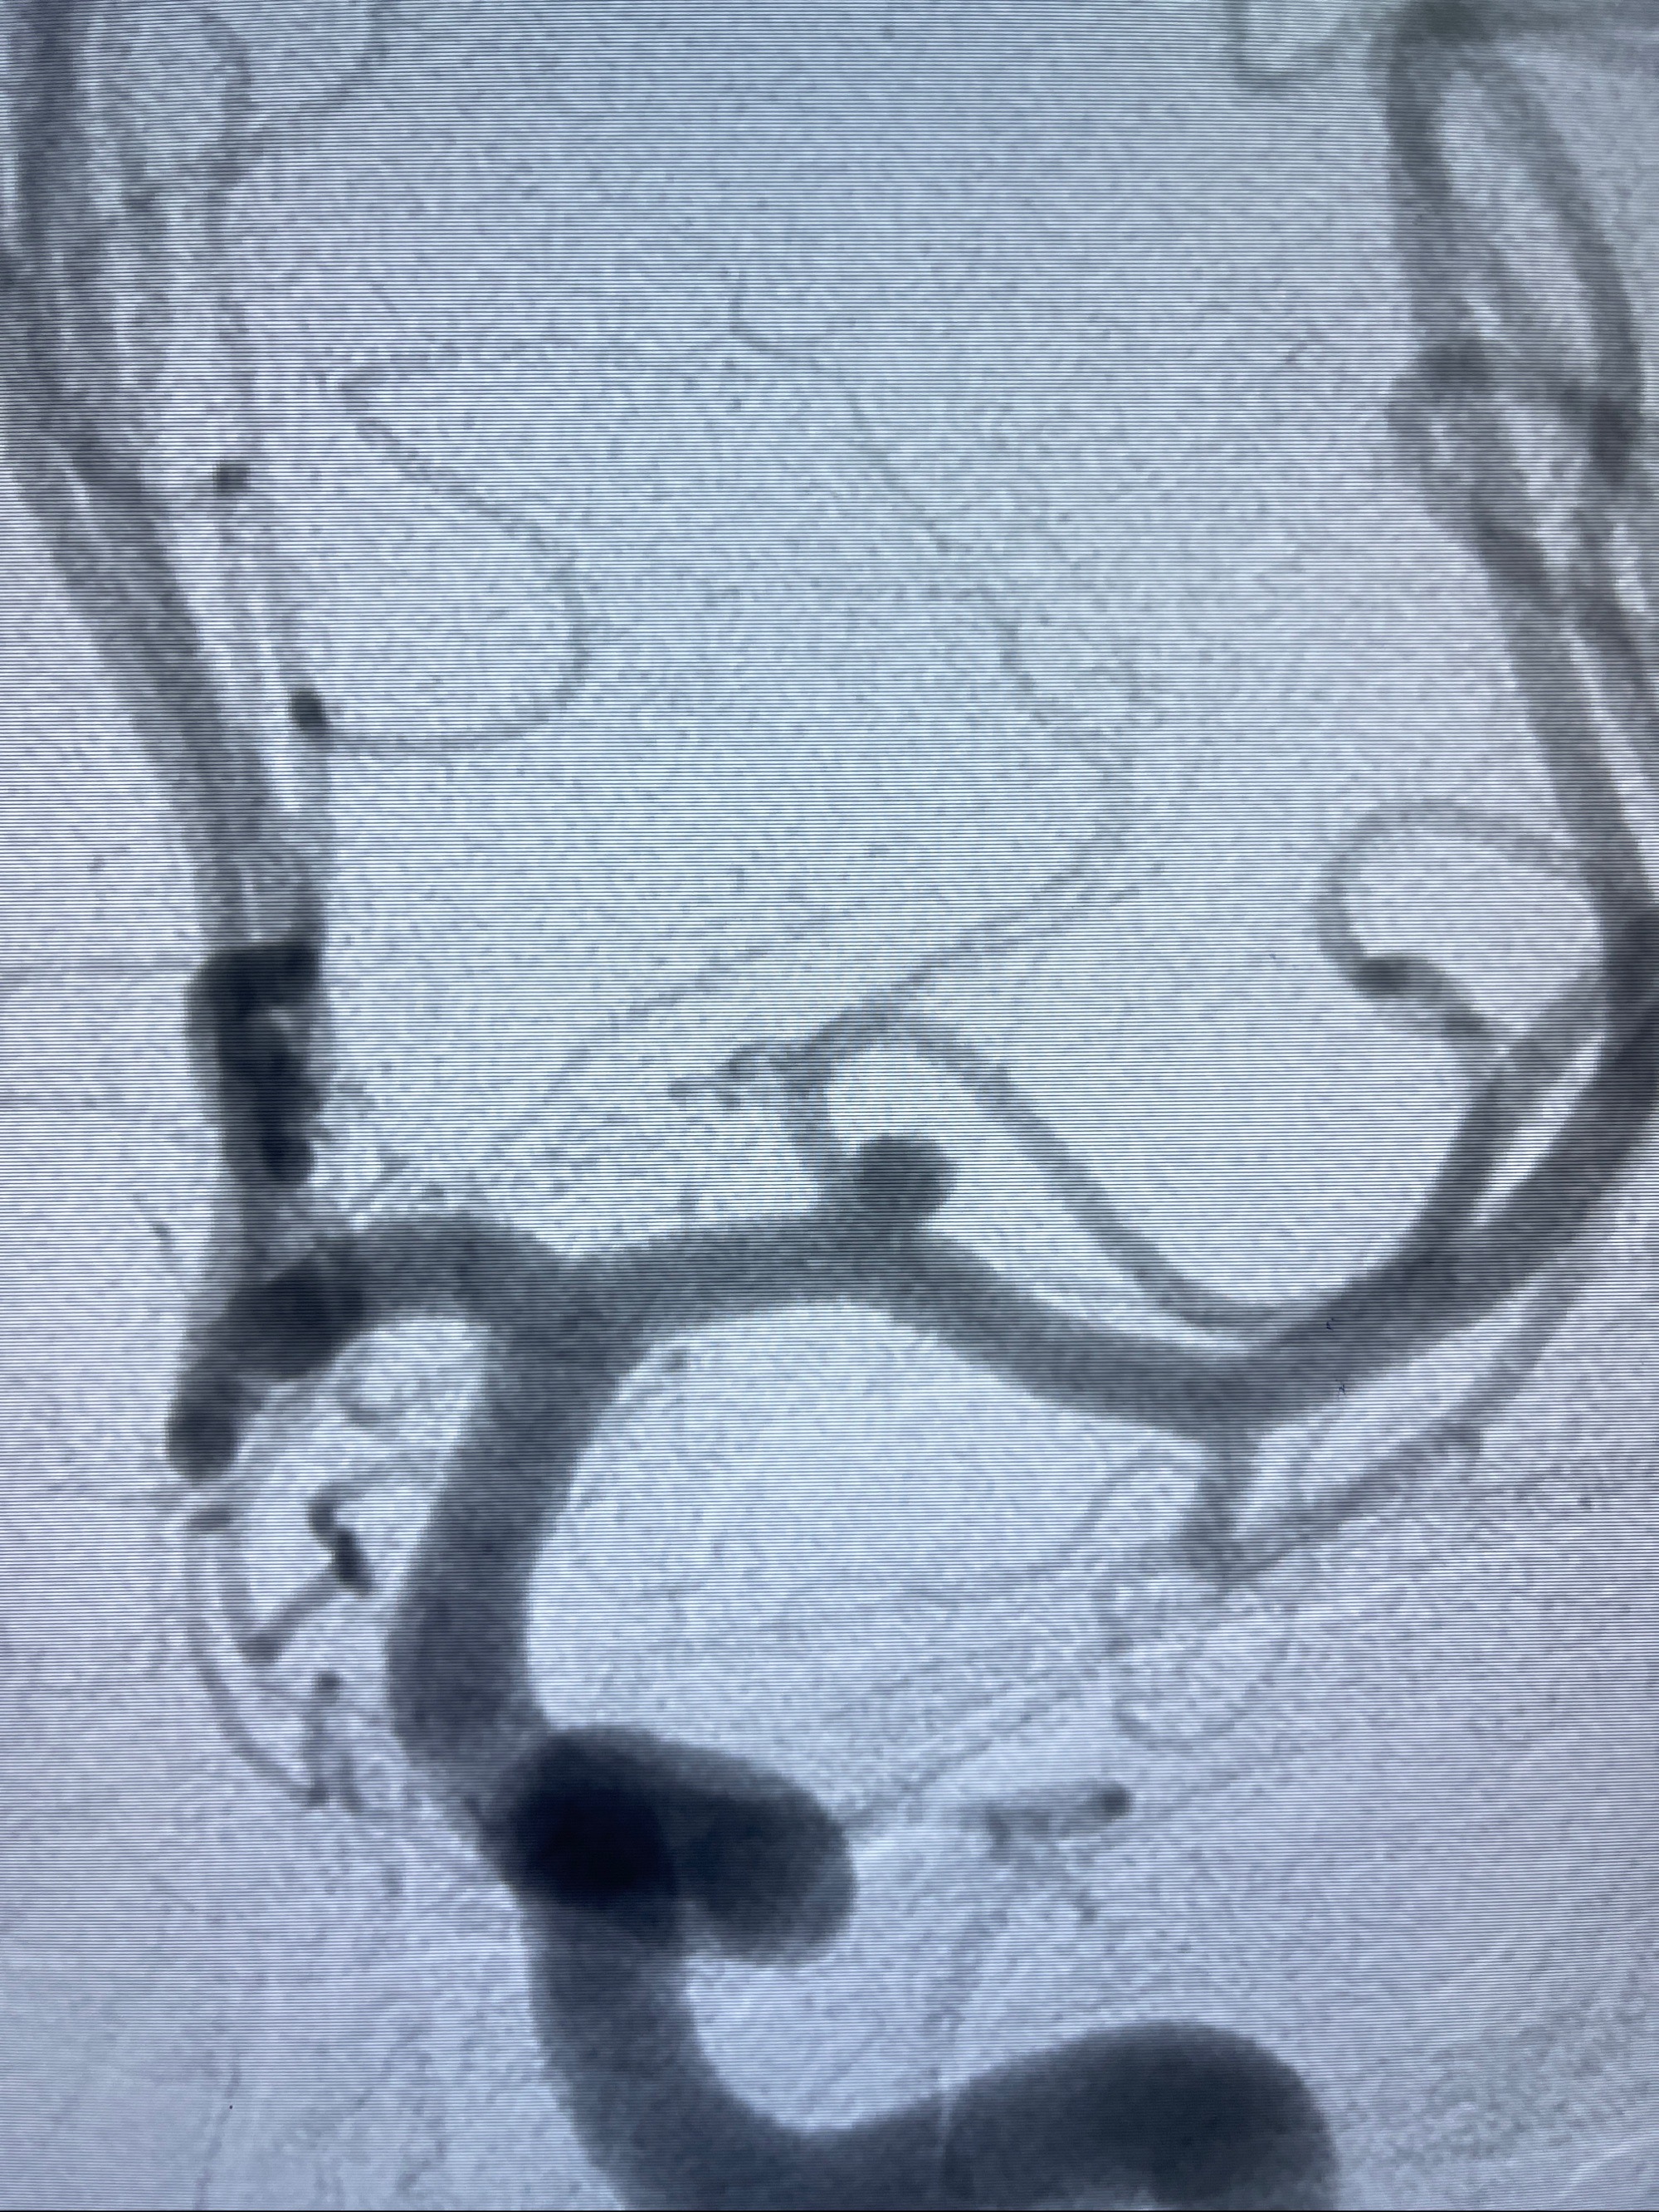

2023-08-14DSA:

左侧大脑中动脉动脉瘤,约2.6-2.8-3.4-2mm大小(瘤颈部、瘤体部、瘤高)

1.左侧大脑中动脉动脉瘤,约2.6-2.8-3.4-2mm大小(瘤颈部、瘤体部、瘤高)

2.外科手术夹闭or介入支架辅助栓塞